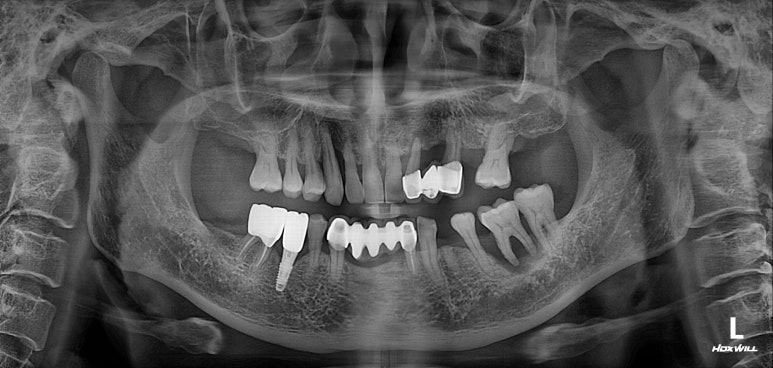

치과용 파노라마 엑스레이입니다.

임플란트가 무려 9개나 되어있네요! 여기에서 앞니 임플란트의 명백한 단점을 확인할 수 있습니다.

보이시나요? 바로 임플란트 크라운이 너~무 길다는 것.

잇몸질환 (만성 치주염)이 심하신 분들의 경우 잇몸뼈의 상실이 심해 결국 임플란트를 '깊게' 심게 됩니다.

결과적으로 치아 길이가 너~무 길어보여 결국 음식도 많이 끼고 비심미적인 (보기 안 좋은) 결과를 낳는다는 것...

사실 어쩔 수 없이 임플란트를 해야만 하는 상황이긴 하나, 잇몸뼈 염증이 심했을 땐 저렇게 어색한 임플란트 머리를 피할 수가 없습니다...

보이시는 것처럼 엄청나게 깊이 임플란트를 심어내고 결국 머리가 엄청 길어져버린 임플란트를 만들어드리게 된단 말이죠...